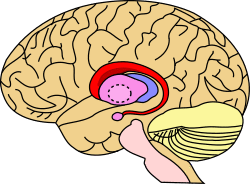

Caudate nucleus.svg

The caudate nucleus is one of the structures that make up the corpus striatum, which is a component of the basal ganglia.[1] While the caudate nucleus has long been associated with motor processes due to its role in Parkinson's disease,[2][3] it plays important roles in various other nonmotor functions as well, including procedural learning,[4] associative learning[5] and inhibitory control of action,[6] among other functions. The caudate is also one of the brain structures which compose the reward system and functions as part of the corticobasal gangliathalamic loop.[1]

Together with the putamen, the caudate forms the dorsal striatum, which is considered a single functional structure; anatomically, it is separated by a large white matter tract, the internal capsule, so it is sometimes also referred to as two structures: the medial dorsal striatum (the caudate) and the lateral dorsal striatum (the putamen). In this vein, the two are functionally distinct not as a result of structural differences, but merely due to the topographical distribution of function.

The caudate nuclei are located near the center of the brain, sitting astride the thalamus. There is a caudate nucleus within each hemisphere of the brain. Individually, they resemble a C-shape structure with a wider "head" (caput in Latin) at the front, tapering to a "body" (corpus) and a "tail" (cauda). Sometimes a part of the caudate nucleus is referred to as the "knee" (genu).[7] The caudate head receives its blood supply from the lenticulostriate artery while the tail of the caudate receives its blood supply from the anterior choroidal artery.[8]